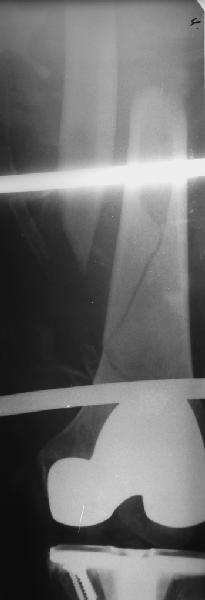

Представляю вам один из наших недавних случаев выполнения малоинвазивного остеосинтеза бедренной кости обычной пластиной 95 градусов. Длина восстановлена с помощью дистрактора (по сути это основная и б(о)льшая часть репозиции). Произведено два небольших доступа, проведена спица направитель. Рентген-контроль для подтверждения достаточной длины/оси (ЭОП использовался в другой операционной). Создание туннеля обратной стороной фиксатора. Поворот фиксатора, введение клинка по спице. Фиксация проксимального и дистального концов пластины.

Получилось очень симпатично, поздравляю и восхищаюсь мастерством.

Хотя закрытый остеосинтез блокированным гвоздем выглядит технически проще, особенно при диафизарных переломах. Не говоря о биомеханических преимуществах внутрикостного имплантата, еще меньшей инвазивности, возможности динамизации при проблемах со сращением... Стоимость гвоздей и пластин сопоставимая, на рынке есть масса отечественных предложений.